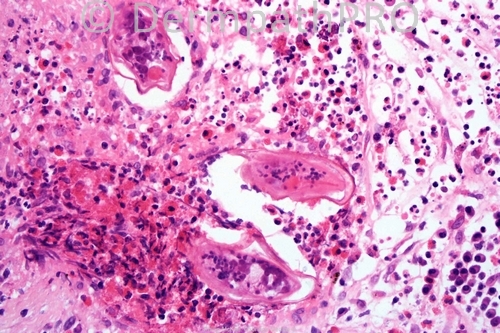

Schistosomiasis

Good morning all. Of course you are all correct. I put this image in because it is so seldom that one manages to see the spine. Well done. Phillip

Apical spine of the eggs is characteristic for S.hematobium type endemic in Middle east and Africa.

Schistosoma eggs within microabscesses containing numerous esinophils. Gorgeous!!!